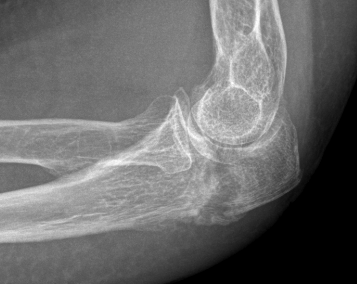

Mayo Classification

A: Non comminuted

B: Comminuted

| Type I | Type II | Type III |

|---|---|---|

| Minimally displaced | Displaced | Trans-olecranon fracture dislocation |

| 10% | 85% | 5% |